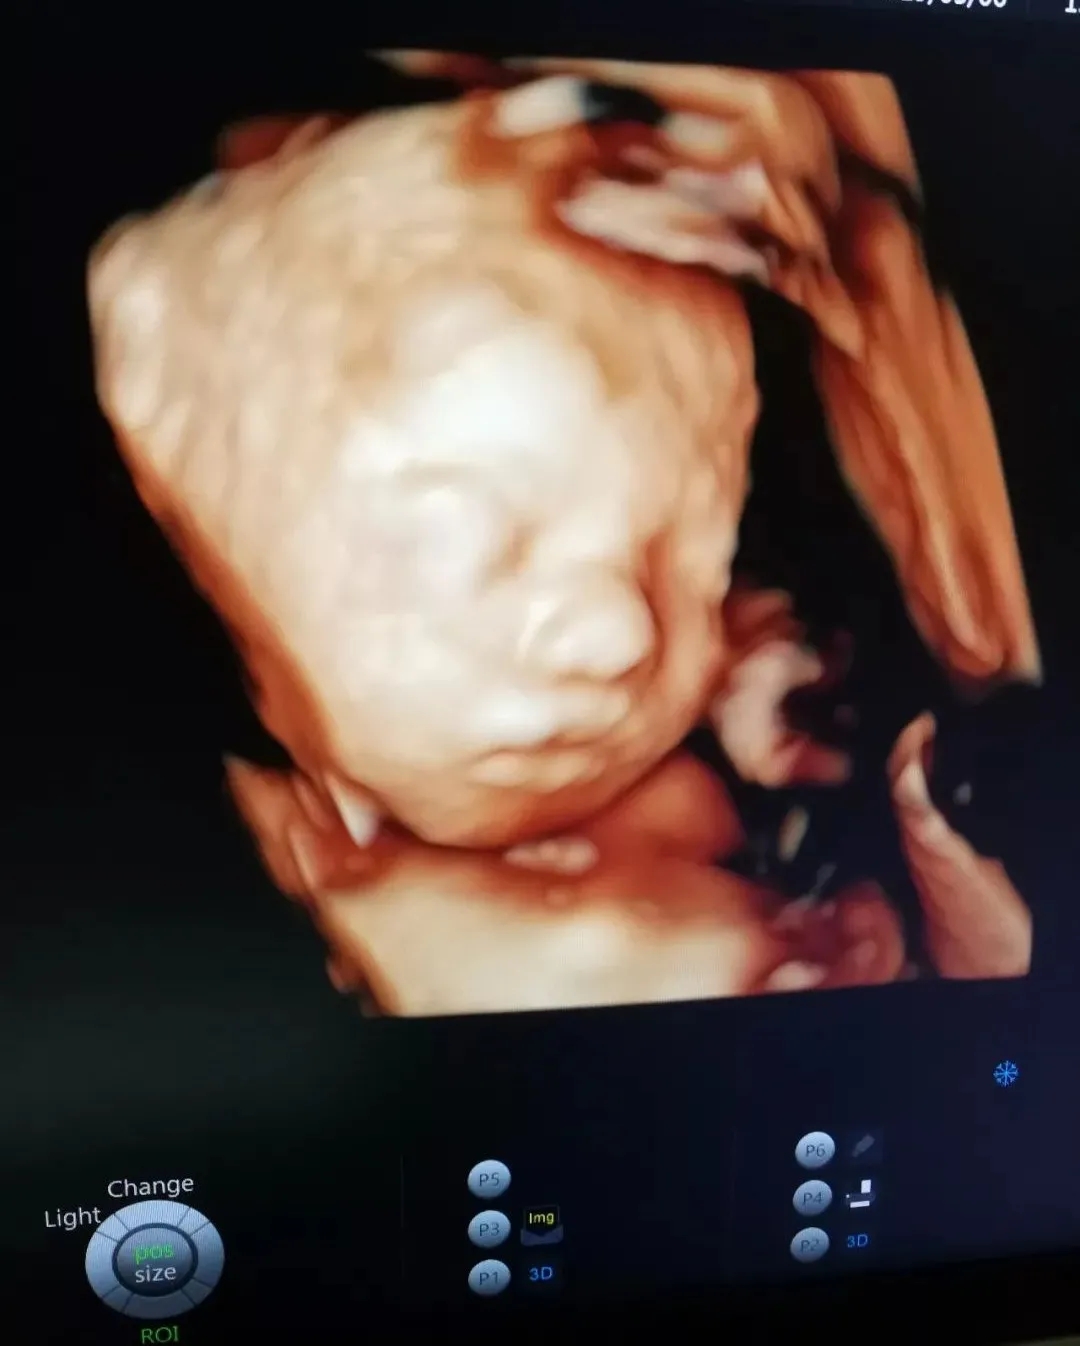

与胎宝紧密相连280天里,一次次胎动是你们之间独特的交流方式,而这时,我们更加好奇胎宝每天都在妈妈肚子里干什么呢?看看这些四维彩超抓拍的胎宝的小模样吧!以下为胎宝的自白时间哦~!

“Hi,妈妈,第一次看到我是不是很惊喜,很幸福~

在刚刚医生阿姨为我做检查时,我能感受到您一直紧绷着,所以,当听见您要见到我第一面的时候,我要送给您一个我的招牌动作~还告诉您一个秘密哦~知道您们在看我,我也很开森~”

但通过美琳达的四维彩超画面中

TA们的活泼好动,萌萌的表情

已经说明了一切